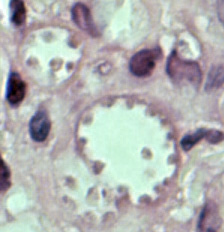

D: Leishmania mexicana

in a biopsy specimen from a skin lesion stained with hematoxylin and eosin.

The amastigotes are lining the walls of two vacuoles, a typical arrangement. The

species identification was derived from culture followed by isoenzyme analysis.

Infection was acquired in Texas.